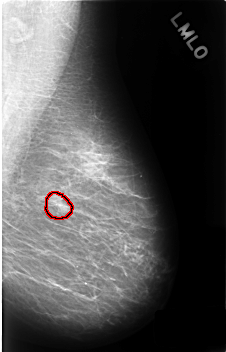

Digital Database for Screening Mammography

Volume: benign_without_callback_02 Case: C-0444-1

C_0444_1.LEFT_MLO

filename C-0444-1

DATE_OF_STUDY 30 6 1995

PATIENT_AGE 51

FILM_TYPE REGULAR

DENSITY 1

DIGITIZER LUMISYS LASER

LEFT_MLO LINES 4568 PIXELS_PER_LINE 2928 BITS_PER_PIXEL 12 RESOLUTION 50 OVERLAY

FILE: C_0444_1.LEFT_MLO.OVERLAY

TOTAL_ABNORMALITIES 1

ABNORMALITY 1

LESION_TYPE MASS SHAPE OVAL MARGINS CIRCUMSCRIBED

ASSESSMENT 3

SUBTLETY 3

PATHOLOGY BENIGN_WITHOUT_CALLBACK

TOTAL_OUTLINES 1

BOUNDARY